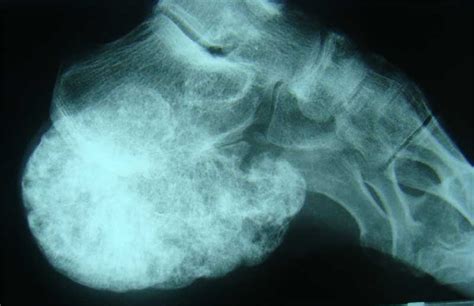

Osteochondroma | Rehab My Patient from www.rehabmypatient.com For them, surgery is not an. Pain in the affected bone is the most common sign of bone cancer. However, you should still check your symptoms and talk to your doctor, as symptoms like bone pain, fractures, swelling, and fatigue can indicate cancer or another issue that needs to be treated. Swelling and redness (inflammation) over a bone, which can make movement difficult if the affected bone is near a joint. Here are symptoms of rheumatoid arthritis you should never ignore. This way, you also avoid more costly cancer treatment. More commonly diagnosed is secondary bone cancer. This is called referred pain.

Bone cancer is rare, making up less than 1 percent of all cancers. Bone infection in foot is relatively common, especially in the presence of other infectious processes in the foot. The american cancer society (acs) can help you connect with others in your area who have bone metastases or with caregivers of people with metastases. If you feel a deep ache in your bone that doesn't go away, you may have bone cancer and you should go directly to bone cancer centers. More commonly diagnosed is secondary bone cancer. Symptoms of a bone tumor in your foot bone tumors of the foot may be painless. This is called referred pain. Bone that is already weakened by a tumor can break, causing severe pain. Any cancer that moves from one. If a bone with a tumor breaks, or fractures, in a leg, it can lead to a pronounced limp. Your doctor uses the needle to remove small pieces of tissue from the tumor. Types of biopsy procedures used to diagnose bone cancer include: In fact, noncancerous bone tumors are much more common than cancerous ones.

This makes it vulnerable for direct infection through punctured wounds and soft tissue infection. Tumors may occur in any bone in the body. Foot injury can cause a tumor to start hurting. It you have bone pain without injury, arthritis, or another explanation, you should be evaluated by your doctor to be sure your pain isn't cause by a serious condition like cancer. Symptoms, a physical exam, and the results of imaging tests, and blood tests might suggest that a person has bone cancer. Bone cancer, also known as osteosarcoma, occurs most often in the long bones of the arms and legs.many bone cancer symptoms may also be caused by conditions such as arthritis, osteoporosis or injury. However, when melanoma does metastasize, one of the most common sites is the skeleton. If you or your child are experiencing persistent, severe or worsening bone pain, visit your gp. Whether primary or metastatic, cancer in the bones may present with symptoms such as increasing pain, swelling and/or a more sudden intense pain from a pathologic fracture —a fracture that occurs in a bone that has been weakened by the presence of tumor. Patients can experience a number of other symptoms if bone metastases affect the bone marrow, which usually occurs in those who have received extensive chemotherapy or radiation therapy. However, you should still check your symptoms and talk to your doctor, as symptoms like bone pain, fractures, swelling, and fatigue can indicate cancer or another issue that needs to be treated. Symptoms like leg pain or joint pain in young children, are often attributed to their active lifestyle, and are brushed aside or dismissed. You can also connect up with a support group.